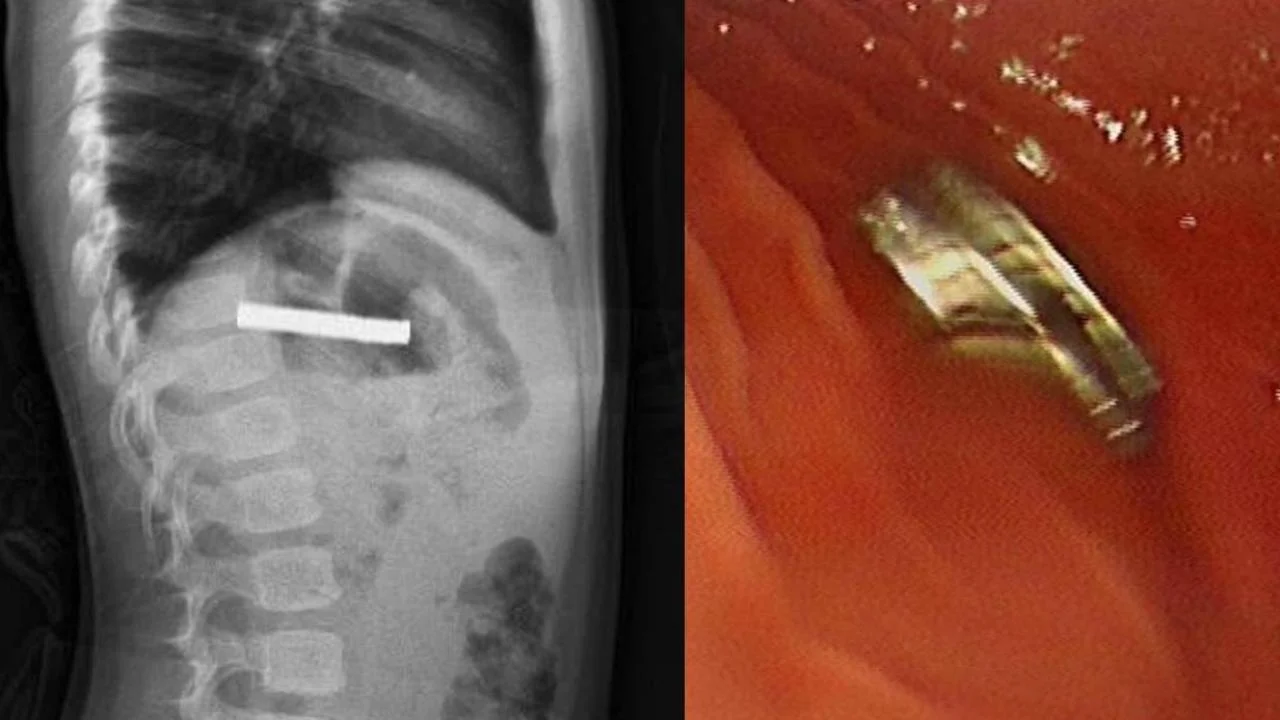

Fırat Üniversitesi Çocuk Gastroenteroloji, Hepatoloji ve Beslenme Bilim Dalı Başkanı Prof. Dr. Yaşar Doğan tarafından yapılan endoskopik işlemle, çocuğun yemek borusuna yapışan 19 mıknatıs tek tek çıkarıldı.

Yemek borusu ve mide girişinde hasar oluştu

Uzun süre yemek borusunda kalan mıknatısların, yemek borusu ve mide girişinde zedelenmelere yol açtığı öğrenildi. Başarılı operasyonun ardından çocuğun sağlık durumunun iyi olduğu ve kısa sürede taburcu edildiği belirtildi.